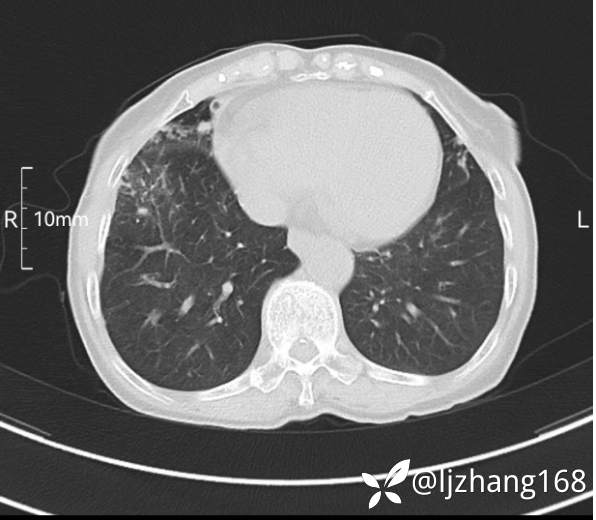

74岁女患,反复咳嗽2月,右肺空洞性病变,炎症OR肿瘤(有病理)

简要病史:2月前开始受凉后出现咳嗽,咳少许白色粘液痰,痰不易咳出,无痰中带血及咯血,无畏寒发热,外院胸部CT提示右下肺空洞病变,脓肿可能性大,常规抗感染治疗效果不佳。既往否认“糖尿病”等病史,有高血压基础病史,无吸烟史。

辅助检查:胸部CT右肺下叶前基底段结节并空洞

临床诊断:右肺空洞:脓肿?